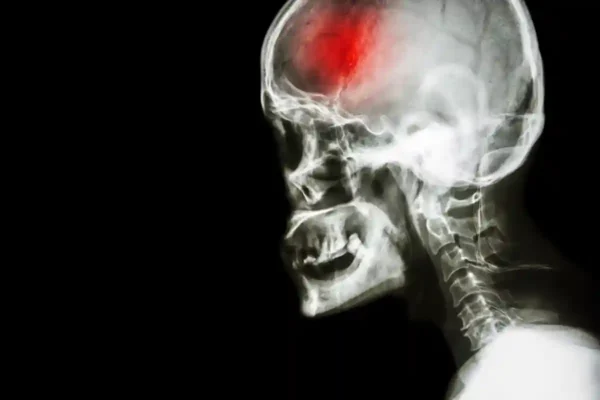

Skubus įspėjimas: du netikėti insulto požymiai, kuriuos privalote žinoti šiandien

Insultas yra viena iš pavojingiausių ir dažniausiai pasitaikančių ūmių smegenų kraujotakos sutrikimų ligų, galinčių smarkiai...

Kodėl pusė lietuvių nepastebi insulto požymių ir kaip išgelbėti gyvybę? Neurologės svarbiausi patarimai

Insultas yra viena greičiausiai kintančių ir pavojingiausių smegenų kraujotakos sutrikimų formų, kuri gali ištikti staiga...

Gyvybę gelbsti pirmieji požymiai: kaip atpažinti insultą laiku ir laimėti kovą su liga

Insultas – tai viena iš pavojingiausių ūmių smegenų ligų, kuri gali pasiglemžti žmogaus gyvybę vos...

Neurologės įspėjimas: kaip atpažinti insulto signalus likus vos 48 valandoms iki jo

Praeinantis smegenų išemijos priepuolis (PSIP) yra laikinas galvos smegenų kraujotakos sutrikimas, kuris dažnai laikomas įspėjamu...

Insultas miego metu: kodėl pavojus dažnai išryškėja tik ryte ir kaip elgtis laiku

Insultas – viena pavojingiausių ir klastingiausių sveikatos būklių, kuri dažnai siejama su staigia mirtimi ar...

Pavyzdiniai insulto požymiai, kuriems nevalia delsti – žinokite, kada kviesti greitąją pagalbą

Insultas yra viena iš pavojingiausių sveikatos būklių, galinčių sukelti rimtų komplikacijų ar net lemti mirtį....

Insulto požymiai, kurių nepastebėjus per kelias valandas prarandama gyvybė – ką būtina žinoti kiekvienam?

Kiekvienais metais Lietuvoje fiksuojama daugiau nei 10 tūkstančių insulto atvejų, iš kurių apie ketvirtį baigiasi...

Insulto požymiai, kurių nepastebėjus – mirtis per valandas: kaip atpažinti ir veikti laiku

Kiekvienais metais Lietuvoje užfiksuojama daugiau nei 10 tūkstančių insulto atvejų, iš kurių maždaug ketvirtadalis baigiasi...